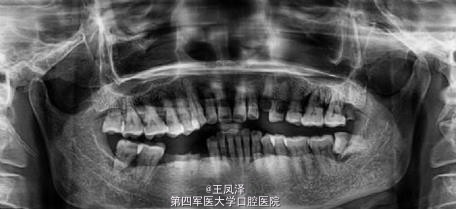

患者,男,59岁,要求做固定修复。44#/45#/46.残根,通过交流沟通选择种植。今天复诊残根拔除3周,要求尽快种植。查软组织愈合不全,但无炎症。告知理论上讲即刻延期需4-6周为好。同意签手术同意书,局麻消毒准备种植。